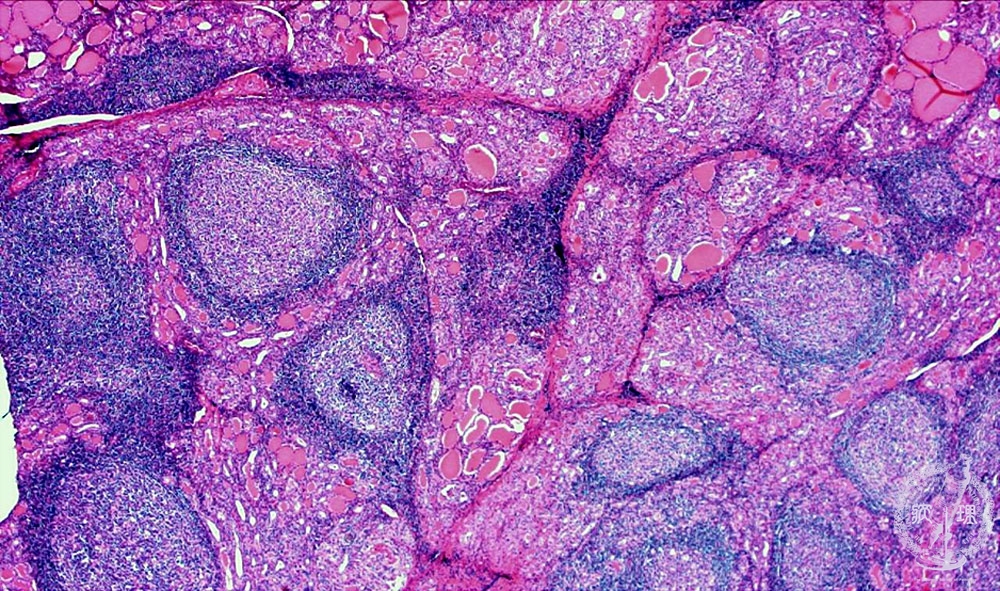

- ★(4)Chronic thyroiditis (Hashimoto disease)

Microscopic findings (HE stain, low power view). Lymphoid follicles (arrows) with germinal center and atrophic thyroid follicles are apparent in the thyroid.